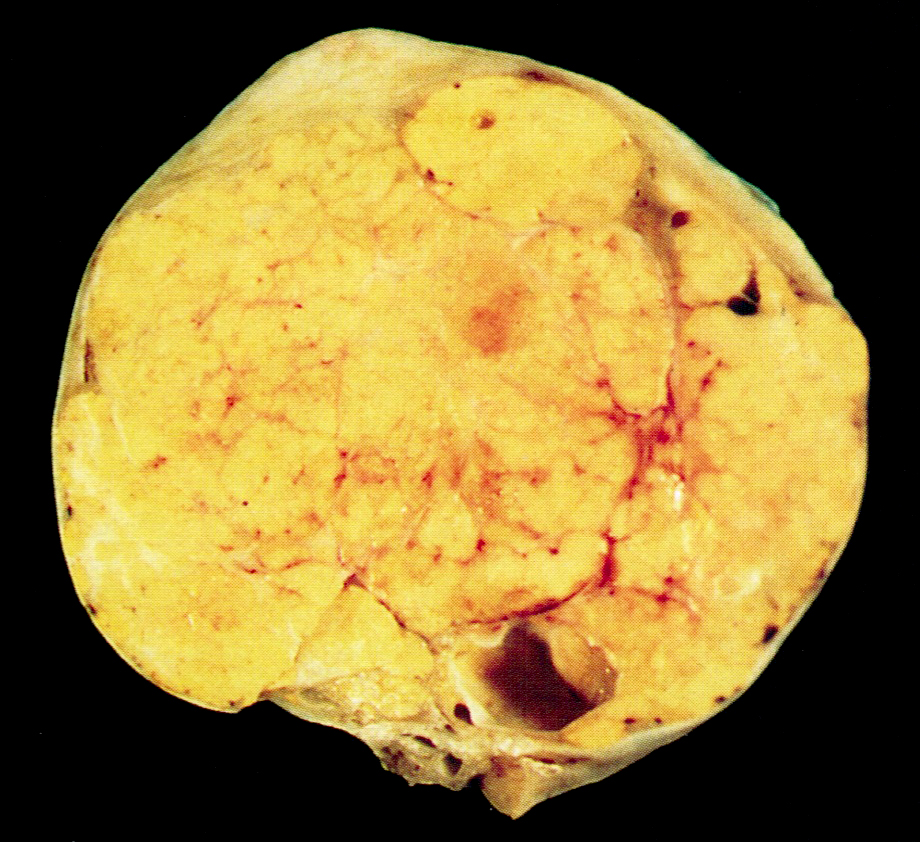

Gross description

- Unilateral, solid, tan to yellow

- Mean size is 8 cm